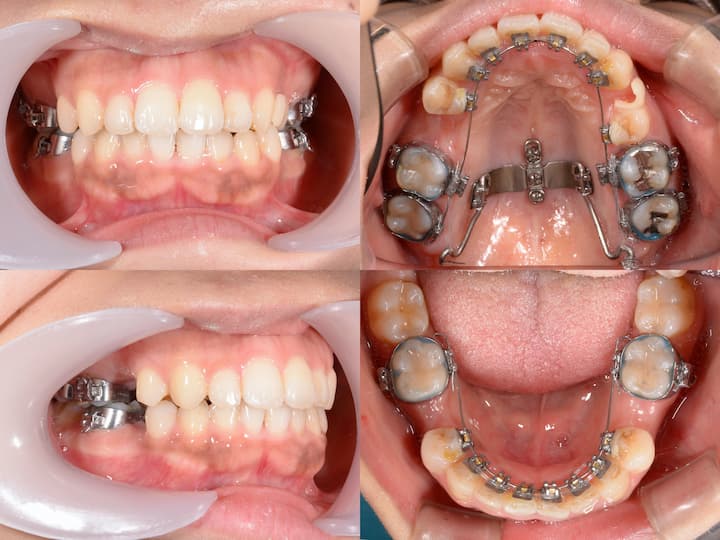

口元の突出感のハーフリンガル矯正

Before

After

治療期間: 1年5ヶ月

上下顎4番を抜歯して、アンカースクリューで大臼歯を固定し、前歯を後方に移動しました。

初診時年齢24歳10ヶ月の患者様です。

口の閉じ辛さと歯の重なりを主訴にご来院されました。

上下左右4番を抜歯してアンカースクリューで上顎6番を固定して前歯を後方に牽引しました。

さらに下顎骨が後方位だったため、上顎大臼歯を圧下(上方向に移動)して下顎骨の前上方への回転を促しました。

本症例は治療期間が1年5ヶ月と比較的短く、前歯の移動量が大きいことから後戻りリスクが高くなります。

フィックス型リテーナーで前歯を固定して、その上から1.0mmのマウスピースで後戻りを防止しています。